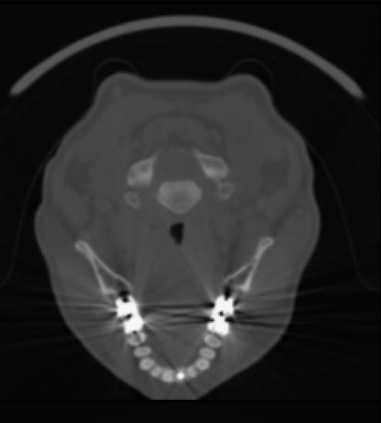

Sparse-view computed tomography (CT) -- using a small number of projections for tomographic reconstruction -- enables much lower radiation dose to patients and accelerated data acquisition. The reconstructed images, however, suffer from strong artifacts, greatly limiting their diagnostic value. Current trends for sparse-view CT turn to the raw data for better information recovery. The resultant dual-domain methods, nonetheless, suffer from secondary artifacts, especially in ultra-sparse view scenarios, and their generalization to other scanners/protocols is greatly limited. A crucial question arises: have the image post-processing methods reached the limit? Our answer is not yet. In this paper, we stick to image post-processing methods due to great flexibility and propose global representation (GloRe) distillation framework for sparse-view CT, termed GloReDi. First, we propose to learn GloRe with Fourier convolution, so each element in GloRe has an image-wide receptive field. Second, unlike methods that only use the full-view images for supervision, we propose to distill GloRe from intermediate-view reconstructed images that are readily available but not explored in previous literature. The success of GloRe distillation is attributed to two key components: representation directional distillation to align the GloRe directions, and band-pass-specific contrastive distillation to gain clinically important details. Extensive experiments demonstrate the superiority of the proposed GloReDi over the state-of-the-art methods, including dual-domain ones. The source code is available at https://github.com/longzilicart/GloReDi.